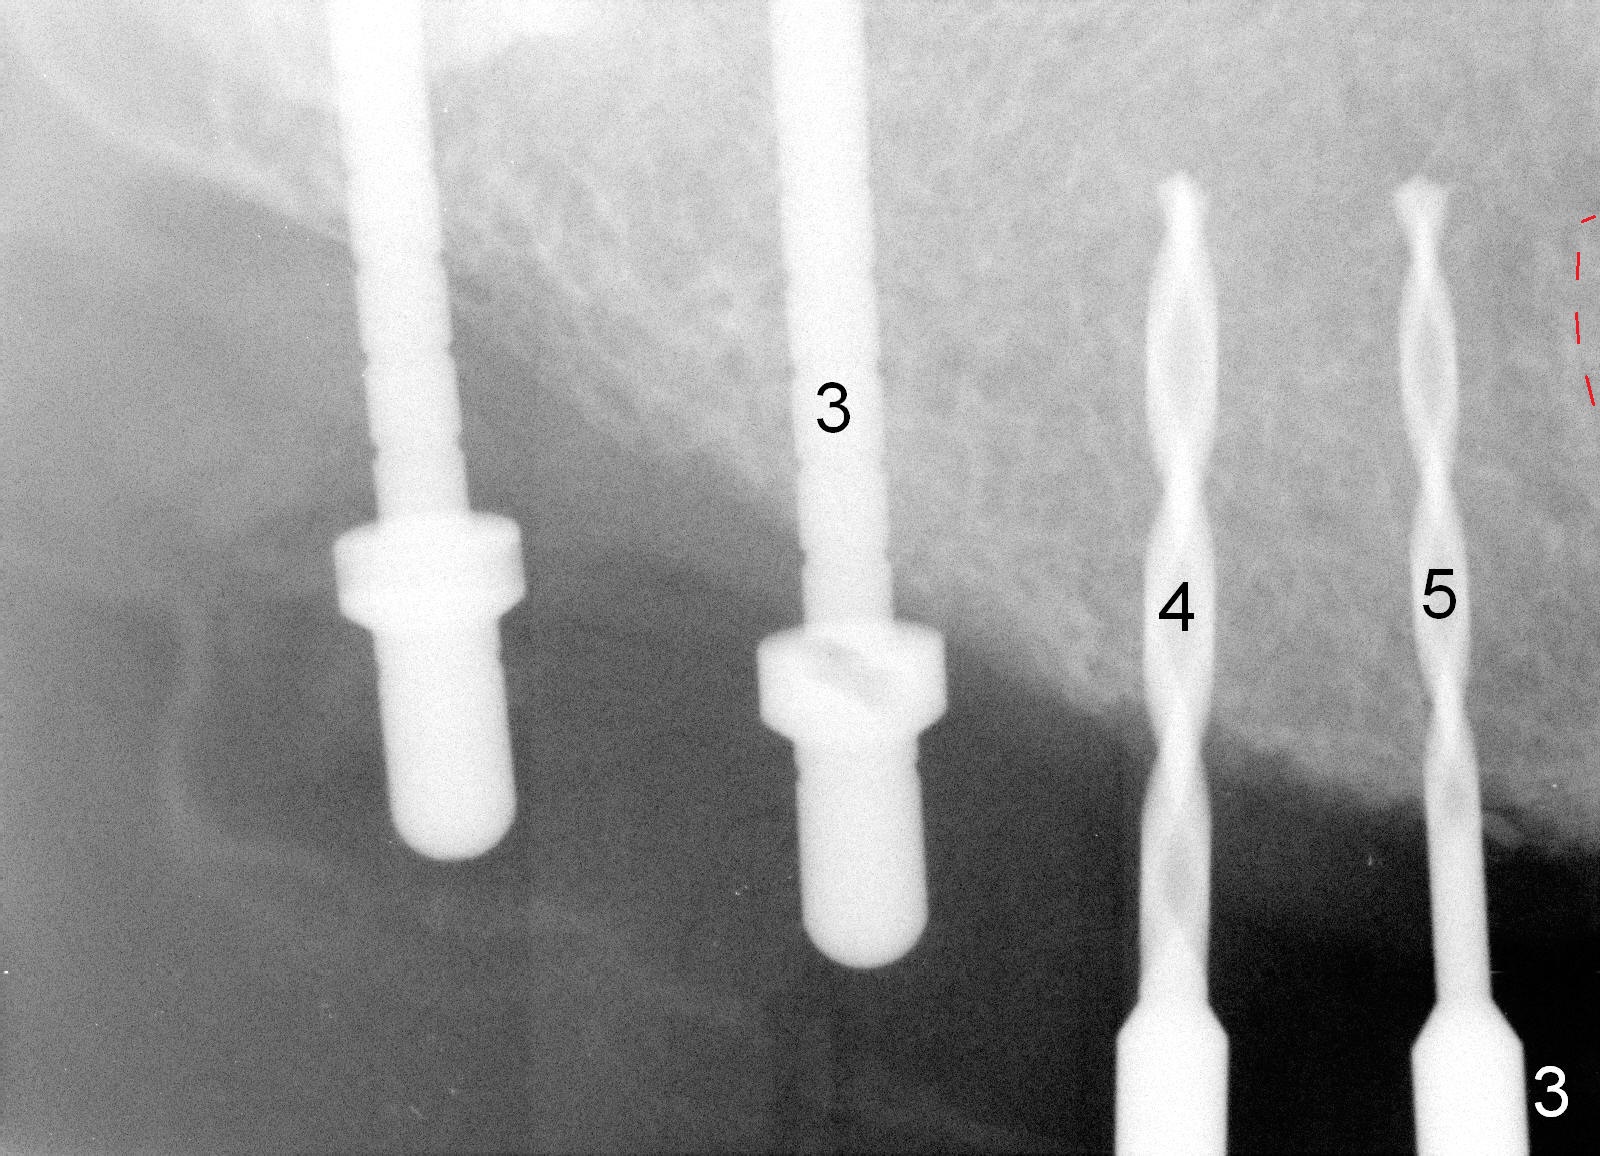

Osteotomy in the upper posteriors starts through a surgical stent for 12 mm.  After incision, each osteotomy is examined, adjusted and extended 2 mm shy of intended (Fig.1,2).  It appears that the trajectories at #4,5 are off (Fig.2).  After re-adjustment, the trajectories are acceptable (Fig.3 (red dashed line; part of the root of the tooth #6)).  Four implants are placed basically in accordance with the plan: 5.9x10 mm at #2, 5x14 at 3, and 3x14 mm 1-piece at 4 and 5 (Fig.4,5).  Fig.6 shows the narrow ridge at #4 and 5 after implant placement.  Although abutments are placed at #2 and 3, an immediate provisional bridge cannot be fabricated because of lack of enough clearance (supraeruption of the opposing dentition).